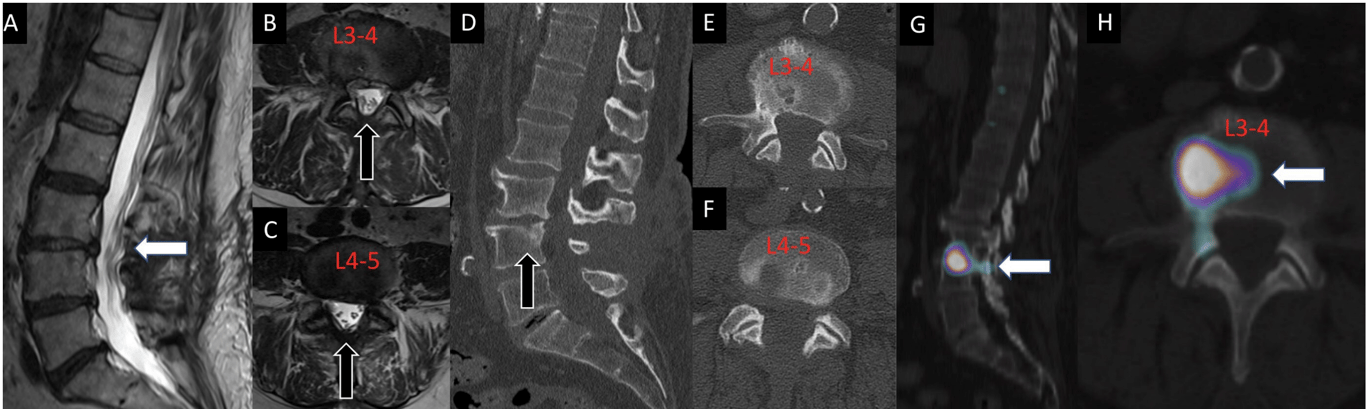

A 70-year-old man had previously undergone L3 to L5 decompression for lumbar spinal stenosis with leg dominant radicular pain. After the decompression, the patient presented with a new complaint of axial flexion-dominant mid-lumbar pain in the absence of leg symptoms. Advanced imaging demonstrated no significant residual/recurrent stenosis on sagittal and axial T2-weighted MRI sequences (A, B, C) and appropriate decompression on sagittal and axial computed tomography images without evidence of pars interarticularis fracture or subtotal facetectomy (D, E, and F). Single photon emission computed tomography with computed tomography findings demonstrated increased radiotracer uptake in the L3 to L4 disc (G and H). The L3 to L4 disc was determined to be the dominant pain generator, resulting in a discogenic pain pattern. The patient was then referred for further physical therapy and physical medicine and rehabilitation.